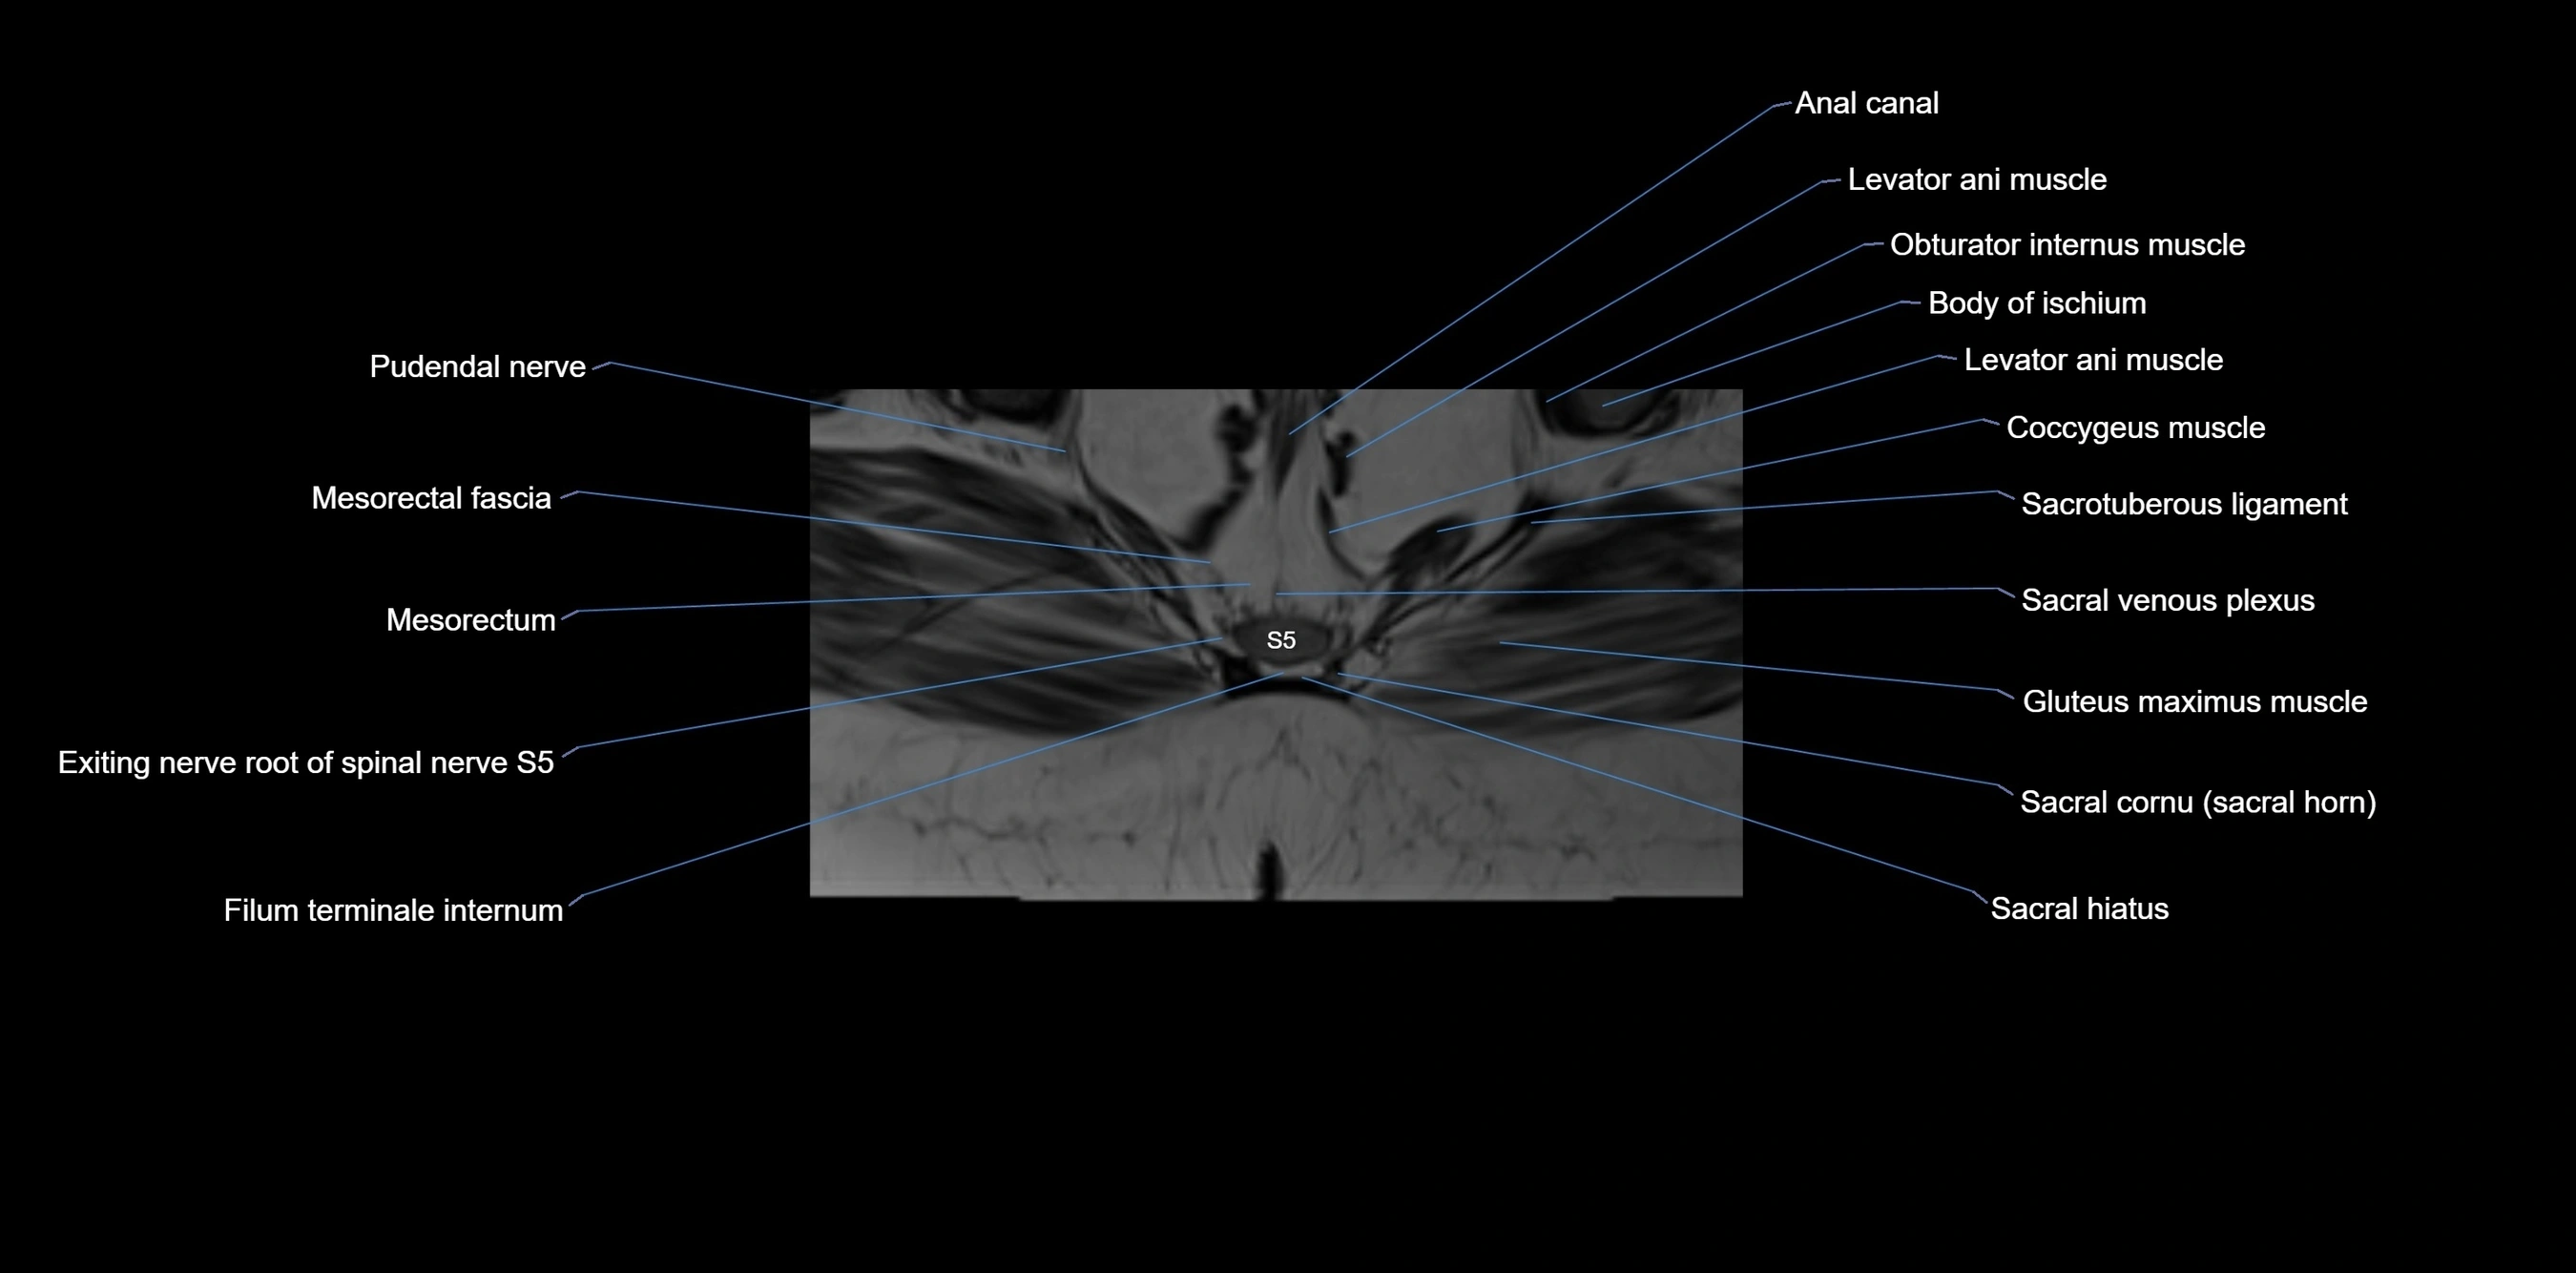

MRI image

image